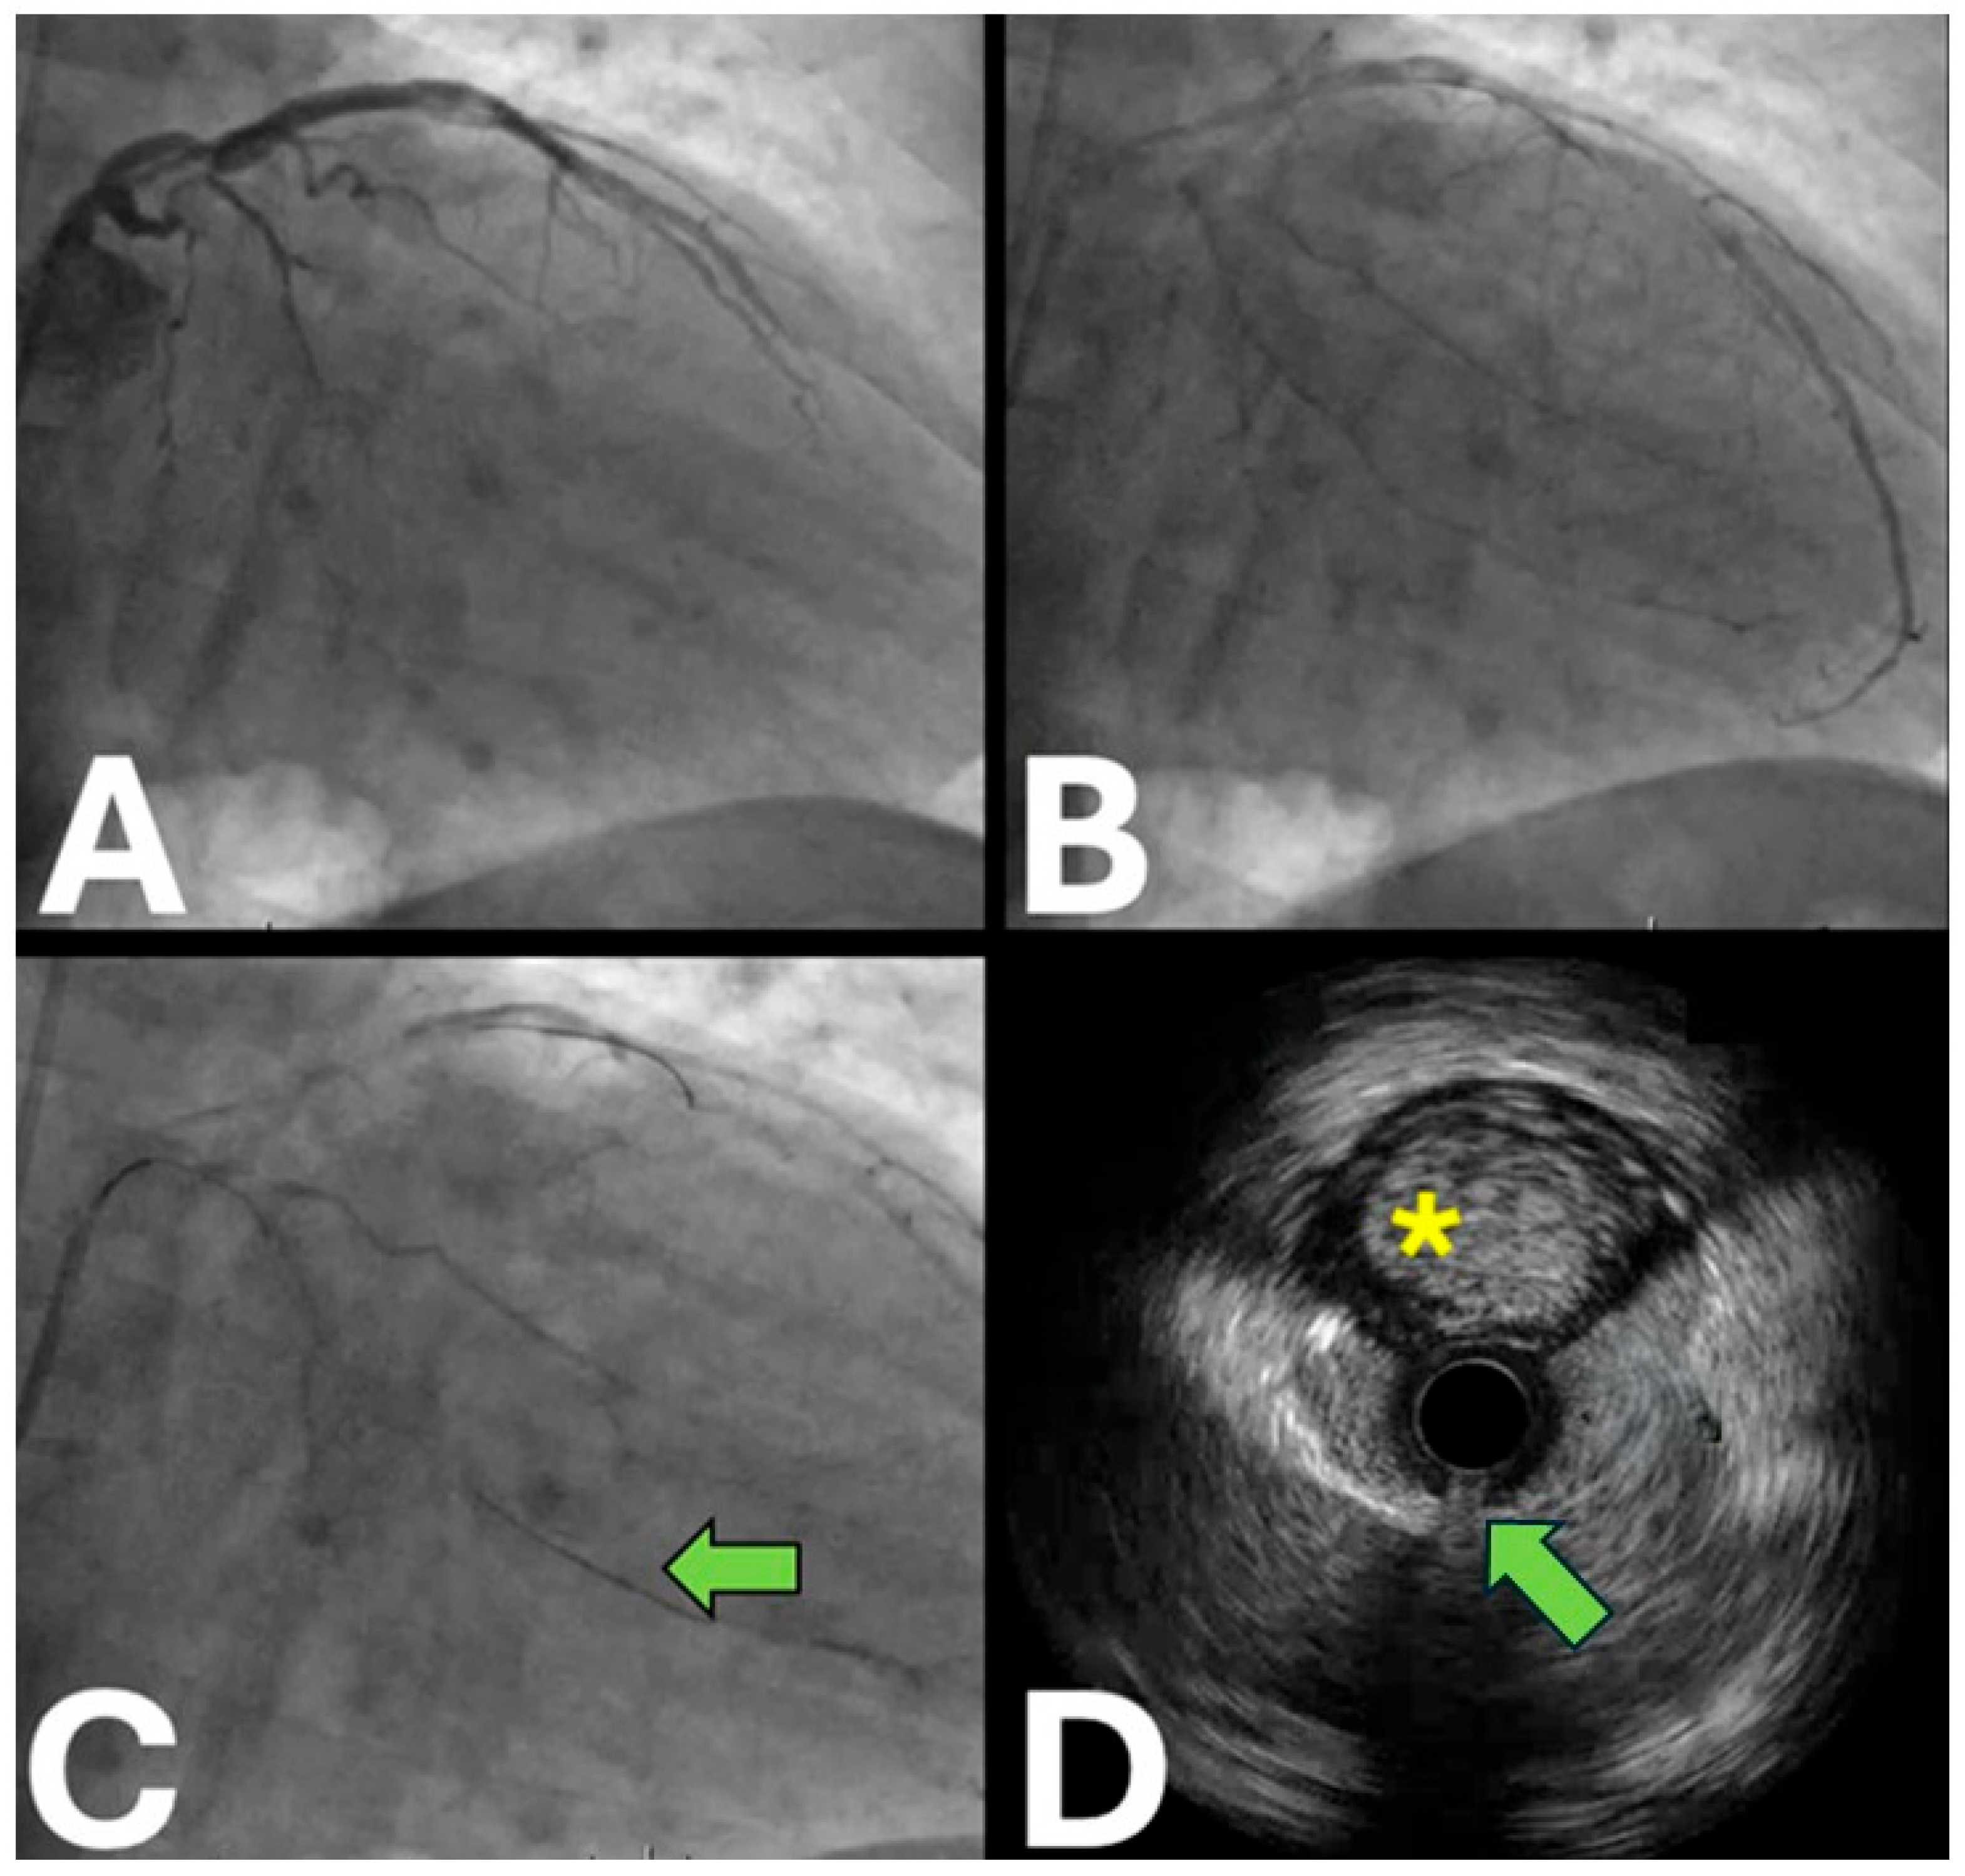

- Proximal cap puncture

- Antegrade wiring

- Antegrade dissection and re-entry

2.2. IVUS Applications in the Retrograde Approach

- Retrograde wiring

- Reverse controlled antegrade retrograde tracking